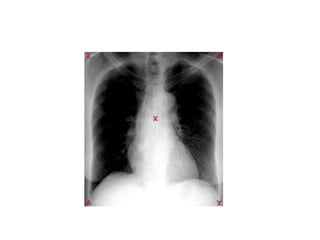

Rx Torax

• Nombre Y Fecha

• Bípeda

• Centrada

• Buena penetración : T4

• Bien Inspirada: Arcos costales anteriores 6-7-

Posteriores 10-11

• Evaluación Radiológica